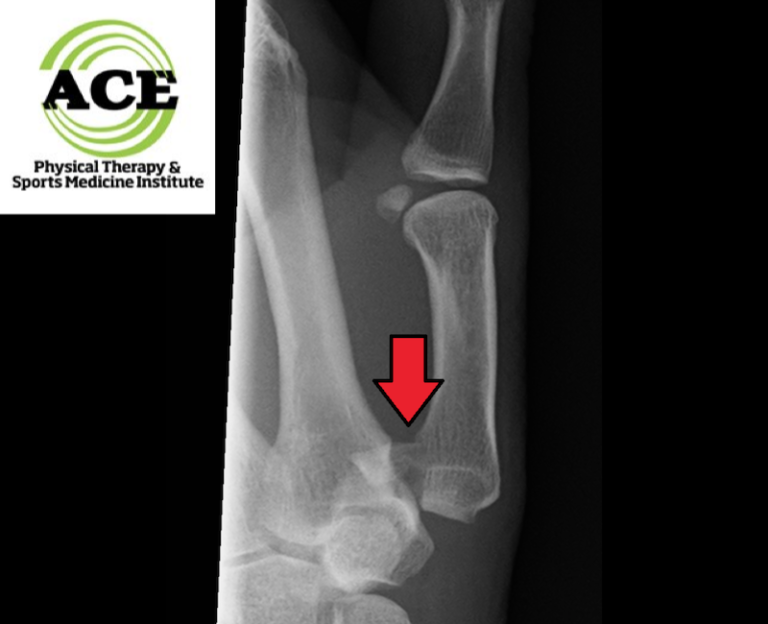

Bennett's Fracture X Ray . This fracture refers to an intraarticular fracture that separates the palmar. the bennett fracture is the most common fracture involving the base of the thumb. determining the optimal treatment method for bennett’s fractures remain a challenge and has been the subject. They need to be distinguished from epibasal. traction radiography may be used to assess the degree of comminution in appropriate fractures (eg, bennett, rolando,. a bennett fracture is a fracture of the articular surface in the base of first metacarpal bone and is considered as an unstable fracture. It is important to distinguish it. a bennett fracture is a fracture of the base of the thumb resulting from forced abduction of the first metacarpal.

From www.ace-pt.org

Fracture Alexandria Thumb Rehabilitation Arlington Bennett's Fracture X Ray a bennett fracture is a fracture of the articular surface in the base of first metacarpal bone and is considered as an unstable fracture. They need to be distinguished from epibasal. It is important to distinguish it. determining the optimal treatment method for bennett’s fractures remain a challenge and has been the subject. This fracture refers to an. Bennett's Fracture X Ray.